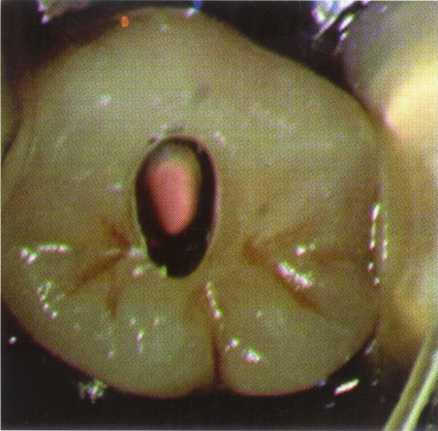

Locating Canals

With complete eradication of the radicular contents, obturation of the radicular space, and good coronal seal to prevent ingress of bacteria, endodontic treatment should approach 100% success. However, this does not occur in reality. The second most common error in access, one that is often not noticed until a recall film is taken or the patient complains of persistent symptoms, is missed canals. The greatest teacher of endodontic anatomy is the microscope. Clinicians have learned that all roots (not teeth) with the exception of #6 through #11 may have two or more canals .z The MB2 canal of the maxil-

lary first molar is commonly referred to as an "extra" canal, but this is not the case-the fifth and sixth canals are the "extras." Without obtaining adequate access in shape, size, and location, locating the exceedingly complex anatomy present in posterior teeth becomes an exercise in futility.

Many of these canals are hidden under dentin shelves, pulp stones, protrusions, and restorative materials. Successful treatment requires adequate access, knowledge of the radicular anatomy, determination, and the assumption of two canals per root until proven otherwise.